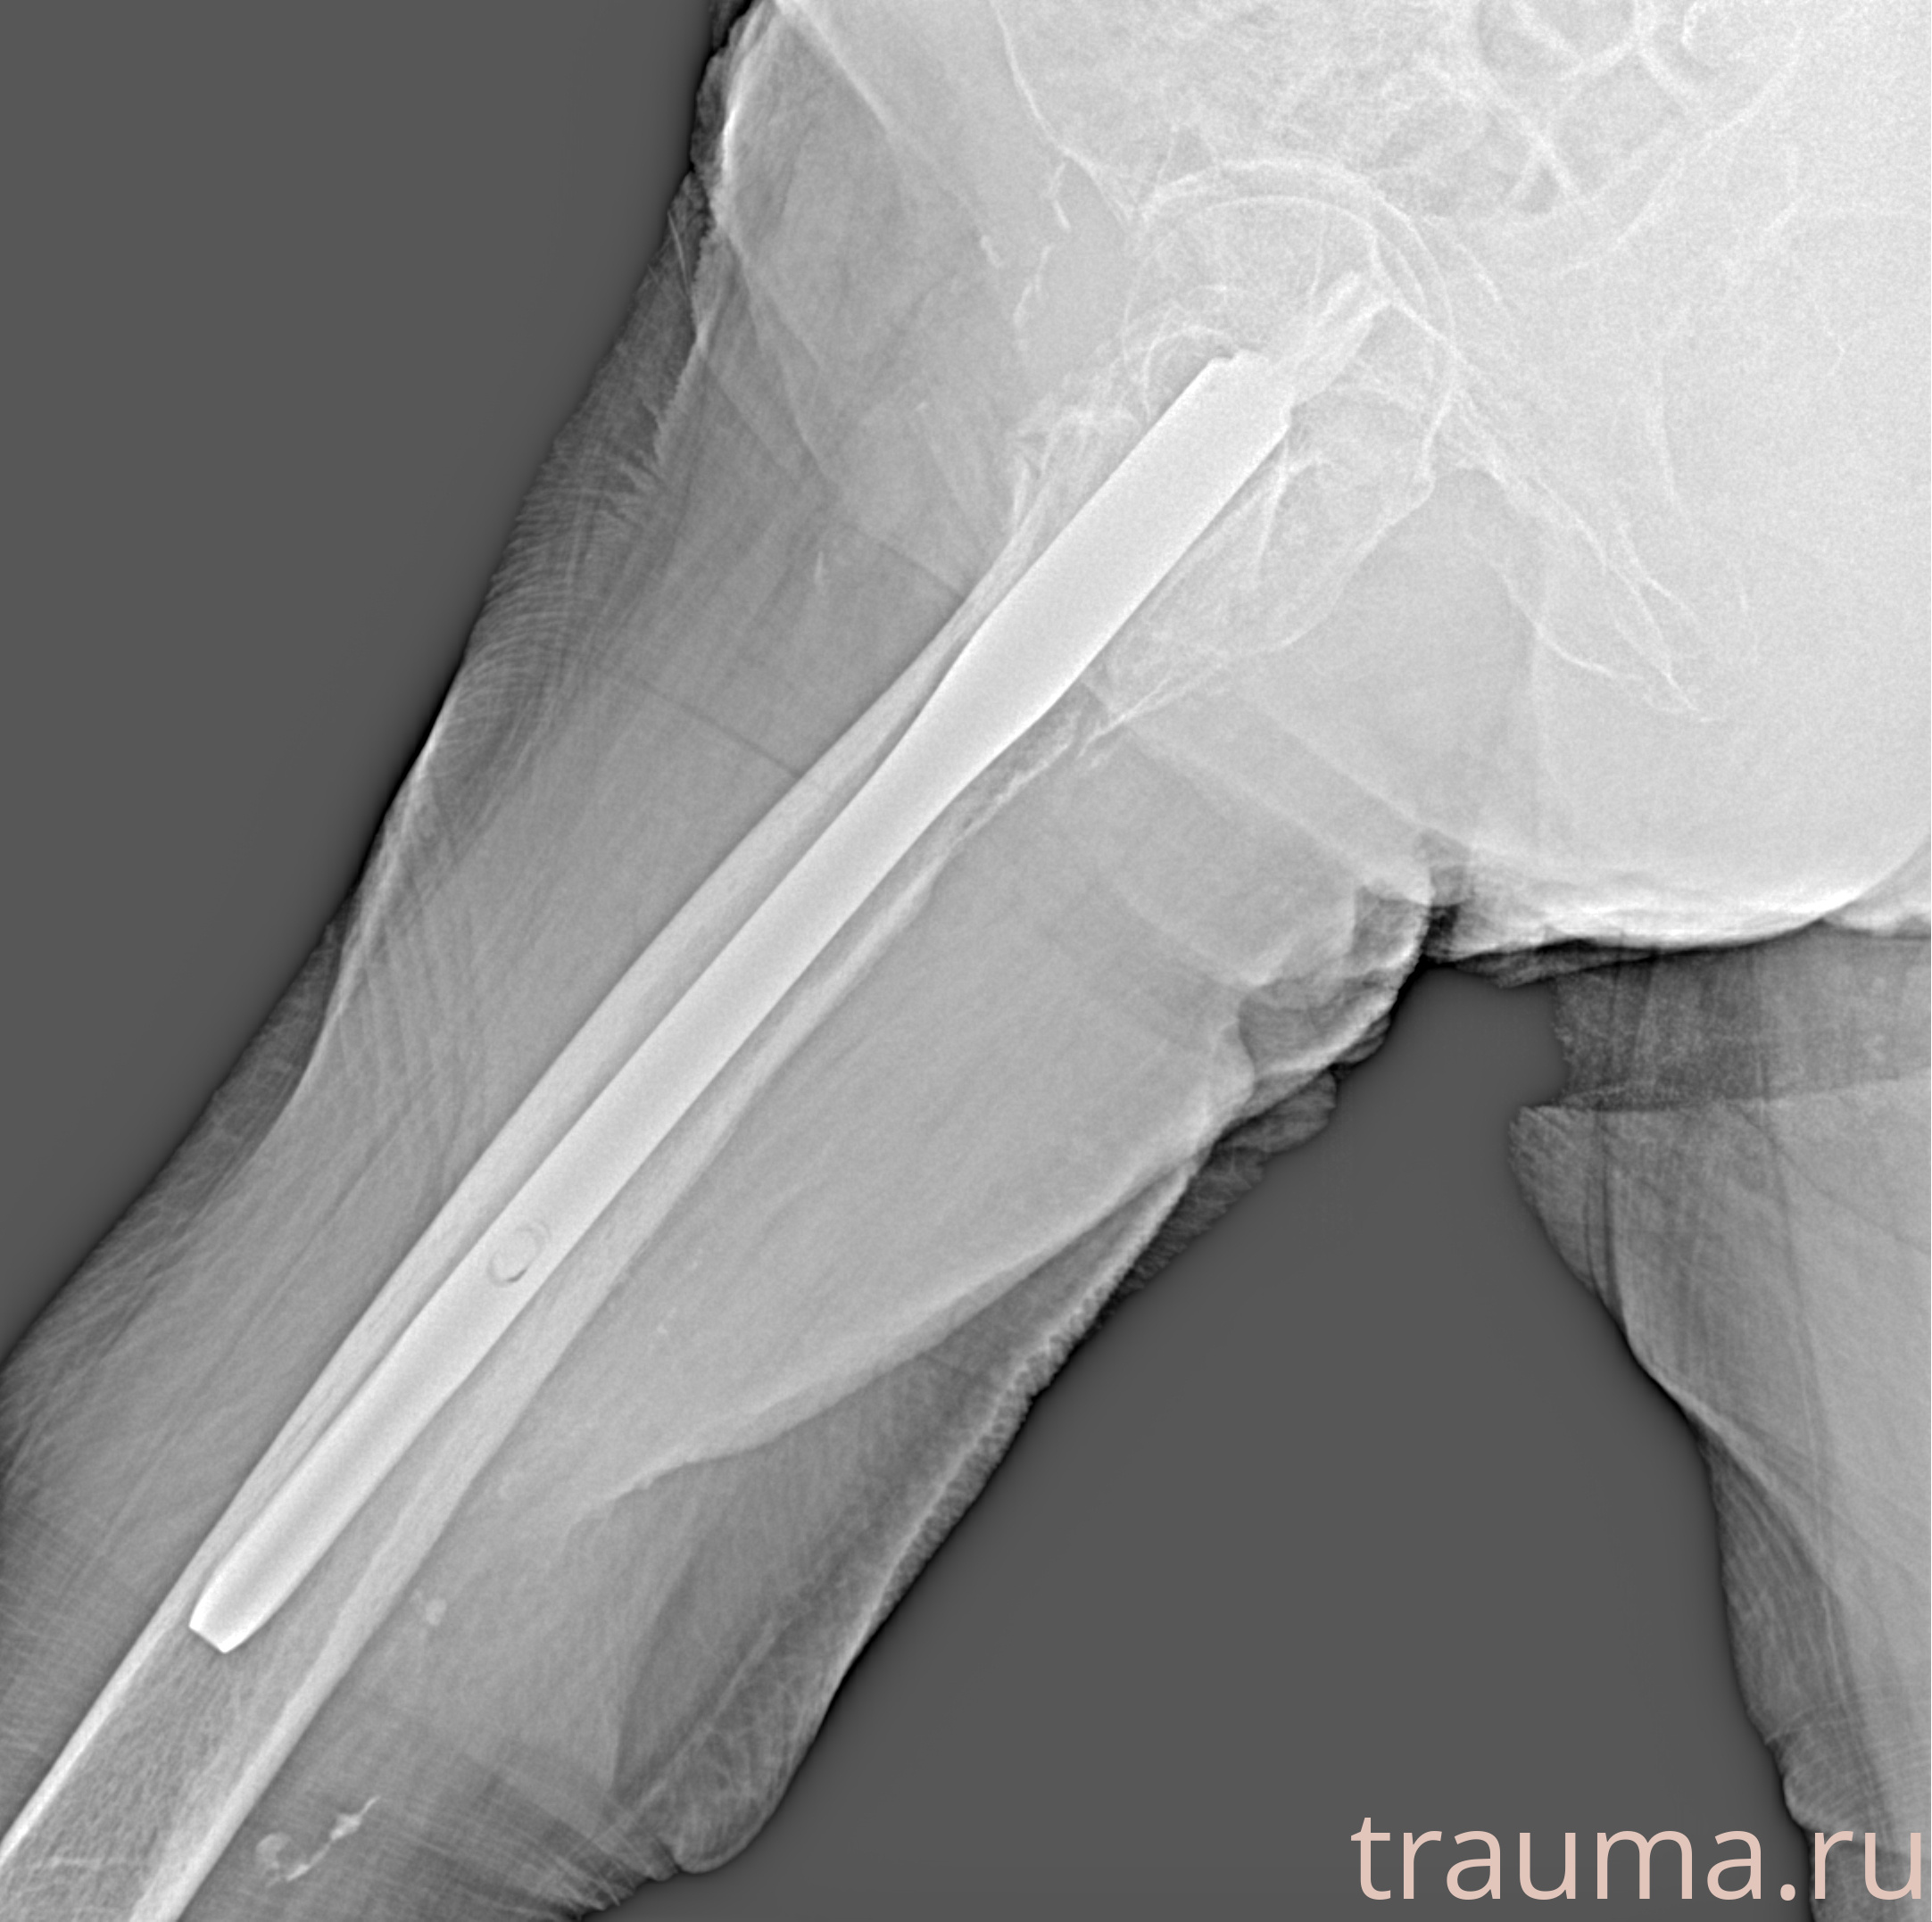

Рентген на дому: по вашему адресу приезжает врач-рентгенолог, травматолог-ортопед с мобильным рентгеновским аппаратом, проводит диагностику травмы или заболевания, делает необходимые рентгенограммы, дает рекомендации по дальнейшему лечению. Получить качественные снимки в домашних условиях возможно благодаря уникальной методике, разработанной МосРентген Центром для института  Склифосовского

при переломе шейки бедра и пневмонии от компании МосРентген Центр - партнера Института имени Склифосовского